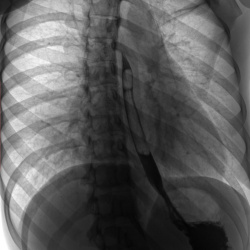

Здравствуйте! Помогите, пожалуйста с диагностикой! Здесь есть каскадный желудок? В заключении написано гастроптоз 3 степени и хронический гастрит. У меня демпингоподобный синдром и гастрокардиальный (головокружение после сладкого, бывает после основного приема пищи, падает давление после еды). Я уже измучилась. У эндокринолога, кардиолога, невролога консультировалась, все говорят это гастроентерологическое. Если надо есть снимки мрт и кт органов брюшной полости. Буду признательна

Не вижу признаков каскадного желудка, не п сал бы гастроптоз, демпинг синдром является осложнением оперированного желудка (нет р-признаков резекции)